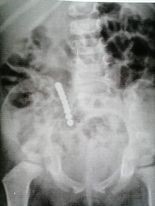

З початку цього року у хірургічному відділенні КНП «Київська міська дитяча клінічна лікарня №2» прооперовано 7 дітей, що проковтнули магніти, віком від 10 місяців до 12 років. Маленька дитина 10 місяців не розуміє що тягне до рота, але дванадцятирічні «кулькоковтателі» насторожують! Практично всі батьки цих дітей не усвідомлювали трагізм ситуації. І це зрозуміло! Скарг немає, як дитина ковтнула магнітик ніхто не бачив, та й дитина не зізнається. Вона активна, бігає, стрибає… ну, була одноразова блювота, «але ж у нас буває ацетон». Психологічно тяжко дати згоду на операцію лише тому, що на рентгенівському знімку є якісь «металеві намистинки». «Вони ж зліпились, яка від них шкода?!», «А є щось більш вірогідне, ніж рентгенівський знімок?», «Дитина здорова, навіщо її оперувати, вам аби різати». Це не повний перелік фраз, що ми чуємо, переконуючи батьків в необхідності операції.

Зрозумійте, між магнітиками защемлені стінки кишківника. Магнітики дуже щільно притягуються один до одного, порушуючи кровообіг в кишці, а це приводить до некрозу і перфорації кишки, до перитоніту.

На щастя тих дітей, ми таки довели необхідність операції. Діти прооперовані. Всі здоровими виписані додому. У всіх 7 дітей був некроз і перфорації на кишківнику. У трьох з них зліплені магнітики, що випали через перфоративні отвори з кишківника, шукали у черевній порожнині й це нагадувало квест «знайди голку в копиці сіна».